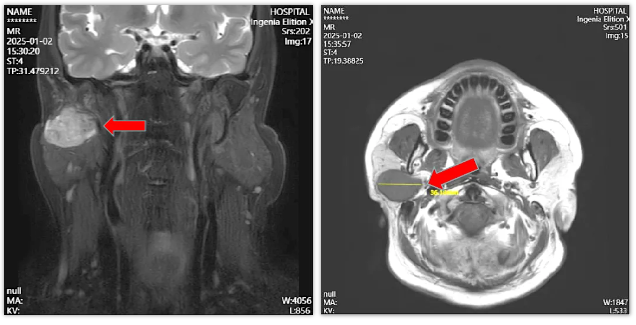

张先生在3个月前偶然察觉自己的面部似乎不对称,用手触摸右侧耳前区能摸到一个巨大的包块,虽然没有疼痛感,但是肿物的存在让张先生担忧不已。张先生怀着忐忑的心情来到我院口腔科门诊就诊,进行了腮腺磁共振检查,结果诊断出右侧腮肿瘤。

针对张先生的病情,赵猛主任团队制定了精确的治疗方案:考虑到患者腮腺肿瘤巨大,且已经突入腮腺深叶,赵主任在手术中仔细解剖出面部神经的各个分支及神经总干,发现腮腺肿瘤紧贴面部神经总干,想要在不伤及神经的前提下切除尤为不易。但赵主任通过精细的操作,成功精确地将患者腮腺浅叶连同瘤体整块切除。整个手术过程顺利,医疗团队考虑到患者尚且年轻,特予以减张美容缝合。术后对肿物进行了病理检查,结果显示该肿物为右侧腮腺多形性腺瘤。术后观察结果表明,团队在术中很好地保护了患者的面部神经,患者无任何面瘫症状。经过医护人员的精心照料,张先生的身体状况逐渐好转,顺利出院。